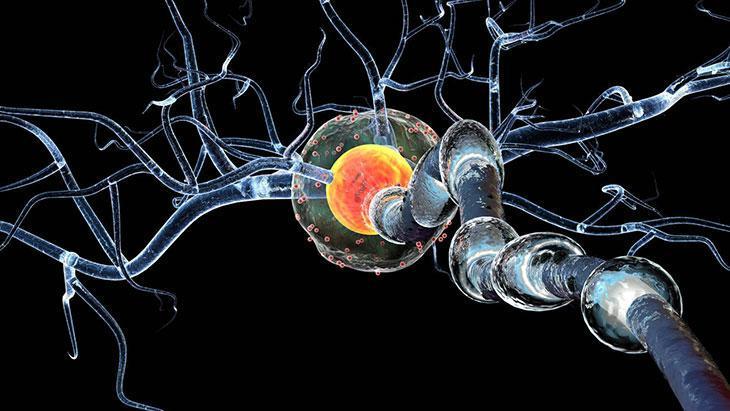

Öncelikle şunu belirtmek gerekir ki bu hastalığa "multipl" denmesinin nedeni, beyin ve omuriliğin birçok farklı alanını etkilemesindendir. Aniden ortaya çıkabilir ya da kaybolabilir. Belirtileri çok çeşitlidir. Hastadan hastaya değişiklik gösterebileceği gibi aynı hastada da zaman içinde farklılaşabilir.

"Skleroz" denmesinin nedeni ise hastalığın beyin ve omuriliğin hasarlı alanlarında sklerozan plaklar yani sertleşmiş dokular oluşturmasıdır. Özetle MS, merkezi sinir sistemini oluşturan beyin ve omurilik üzerinde yıkıcı etkileri olan, kişinin yaşamsal fonksiyonlarını bozan ve ataklarla seyreden bir hastalıktır.

MS, vücudun bağışıklık sistemindeki normal işleyişi bozar. Bilindiği gibi normal şartlarda bağışıklık sistemi bizi hastalıklara karşı korur. Değişik nedenlerle bazen bu sistem vücuttaki normal dokuları da yabancı görmeye başlar ve onlara hücum eder.

Hastalık sinir sisteminin farklı bölgelerini farklı zamanlarda etkileyebilir. İlerleyen hastalık kişinin görme, yürüme, konuşma gibi yaşamsal öneme sahip fonksiyonlarını bozar.